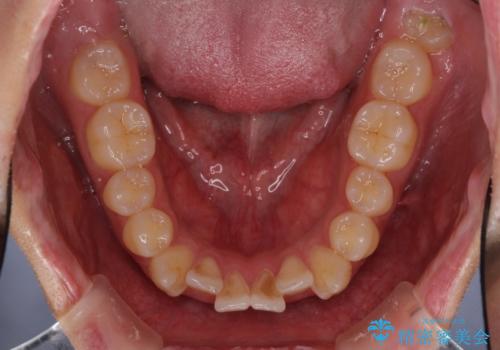

- 前歯の歯並びと不自然な色をした前歯のクラウンを気にして来院された患者様です。

上下前歯の歯列不正はインビザラインにより歯列を整え、その後に、前歯をオーダーメイドタイプのオールセラミッククラウンにて補綴治療することとしました。